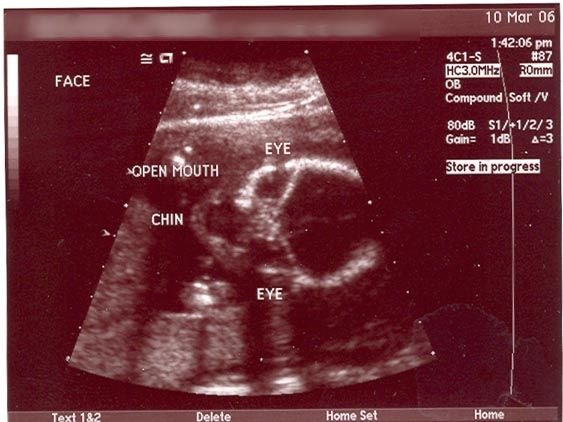

Alien Dad: я чуть не сошел с ума, когда увидел УЗИ своей беременной жены. Я БУДУ ОТЦОМ ИНОПЛАНЕТЯНИНА! Я так горжусь своим пришельцем